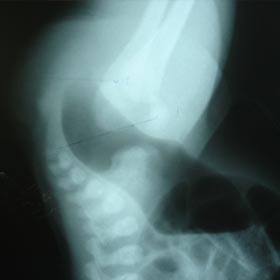

Anorectal Malformations (ARM)

At our hospital, we run Anorectal Malformation clinic for male children with high/low anomalies and female children with vaginal/vestibular fistula's. Again single stage surgery is recommended for majority of anomalies without colostomy.